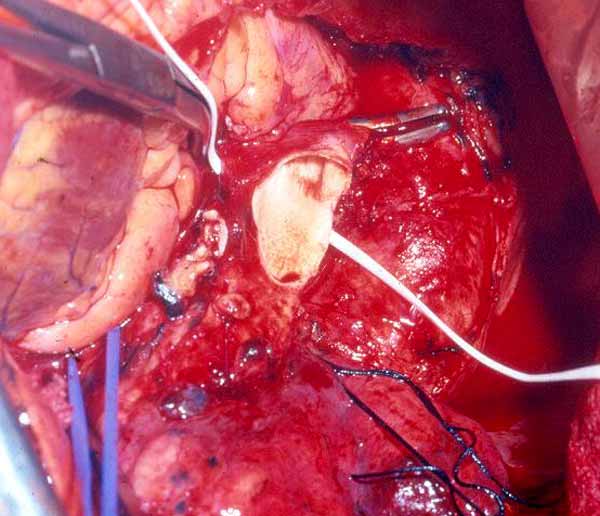

On occasion a sleeve resection of the upper lobe and the pulmonary artery is necessary (Figure 16). Pulmonary artery and inferior pulmonary vein control are obtained as described above. The vascular conduit is constructed from a segment of autologous pericardium (Figure 17). When sizing the conduit, two points must be considered: the PA stumps can be approximated closer than it seems, and the conduit will stretch more than predicted. It is advisable to tailor the length of the conduit on the basis of the resected arterial segment, because the elasticity of the two tissues is comparable. The bronchial anastomosis is performed first to avoid traumatizing the PA (Figure 18). The PA is reconstructed by end-to-end anastomosis with running 5/0 or 6/0 monofilament suture (Figure 19).

| Figure 19: The arterial conduit is interposed (left) and the proximal and distal anastomoses have been completed (right). | |